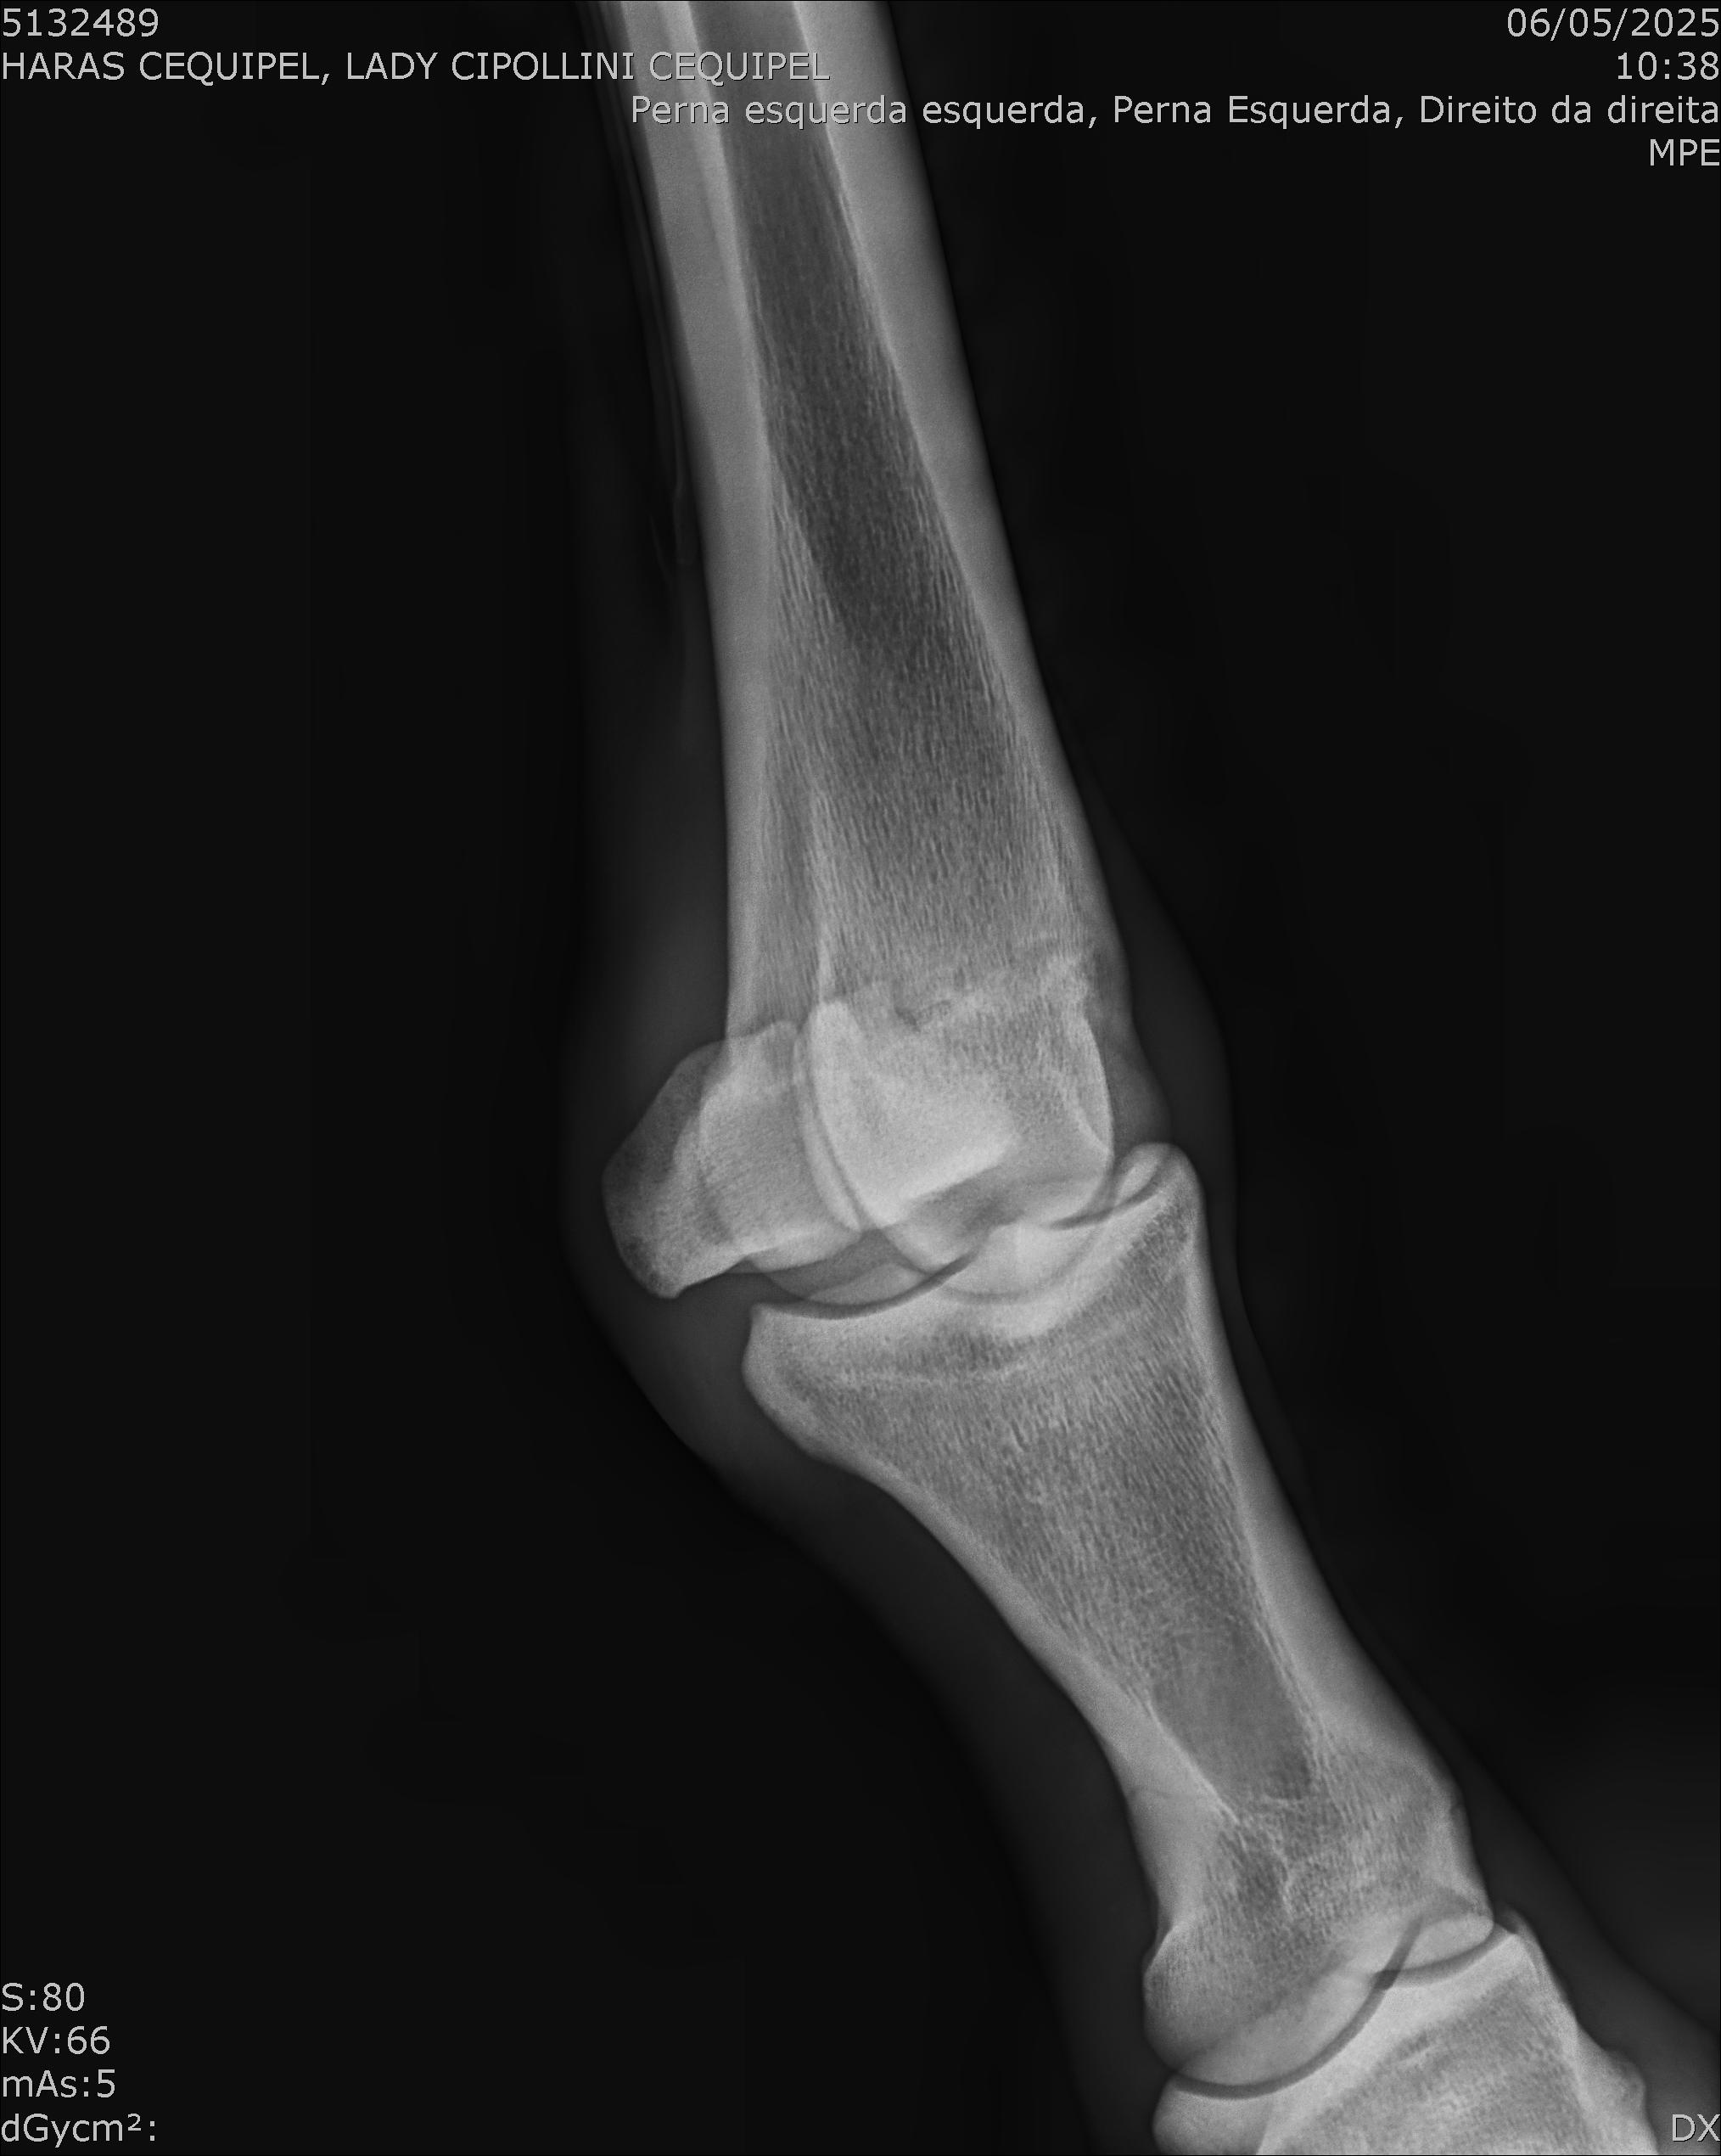

:: RAIOS-X DO LOTE